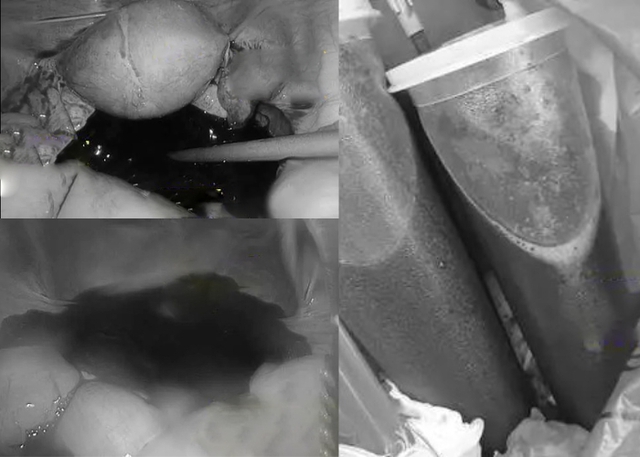

Tiến sĩ Lý Vệ Quân, bác sĩ sản phụ khoa tiếp nhận ca bệnh này cho biết: “Khi nghe mô tả triệu chứng, tôi nghi ngờ ngay khả năng vỡ hoàng thể. Kết quả kiểm tra cho thấy bệnh nhân xuất huyết ồ ạt trong ổ bụng. Lượng máu được hút ra trong ca mổ lên tới khoảng 1,5 lít. Ngoài vùng chậu, máu còn lan rộng trong khoang bụng".

Ê-kíp phải nội soi khẩn cấp, xử lý điểm rách ở buồng trứng, cắt nang hoàng thể và làm sạch ổ bụng. May mắn, buồng trứng vẫn được bảo tồn. Nhưng với tư cách vừa là bạn cấp 3 của người bạn trai, vừa là bắc sĩ điều trị thì Tiến sĩ Lý không thể không trách anh ta vài câu.

Tổng lượng máu trong khoang bụng do vỡ hoàng thể là 1,5 lít (Ảnh BV cung cấp)